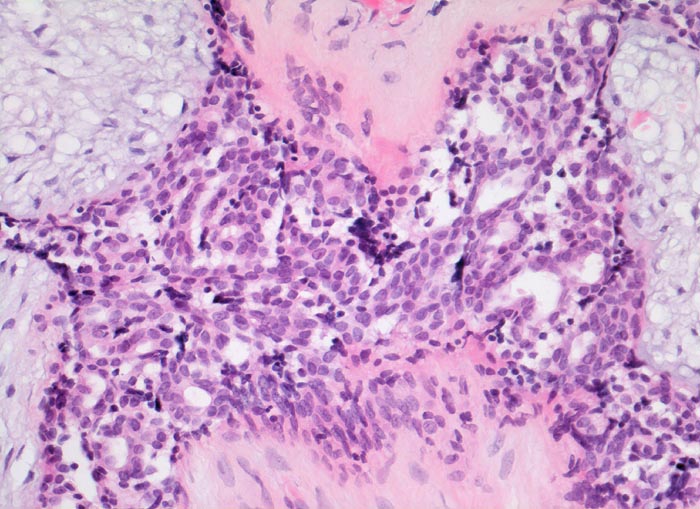

• Stellenweise gewöhnliche intraduktale Epithelproliferation ohne Atypie.

• Die Drüsen werden ausgekleidet von einer inneren kubischen bis hochprismatischen Zellschicht und einer äusseren abgeflachten Myoepithelschicht mit klarem Zytoplasma.